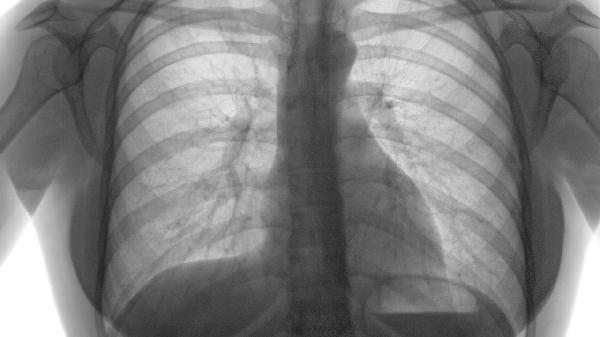

直径超过5厘米的肺大泡或反复气胸发作时,可考虑胸腔镜下肺大泡切除术或肺减容术。术前需评估剩余肺功能,术后需加强呼吸道管理。微创手术并发症发生率低于10%,多数患者症状显著改善。